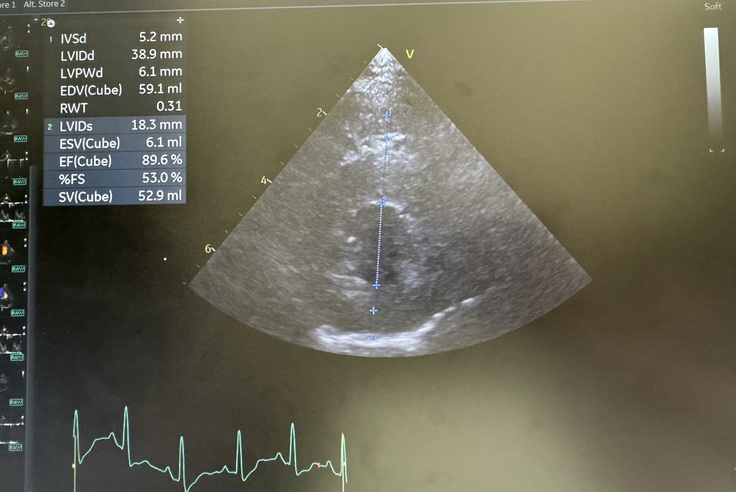

検査が終わりましたが、数値も変わらず心臓も大きいままでした。

薬の作用で一時的に抑えられている部分もありますが、同時に進行もするのでこれからが心配との事でした😭

肺水腫になりかけているので薬もまた増えてしまいました。

水が溜まると現在、ステージCですがDになるので様子を見て異変があればすぐに連絡ください。と言われました🥲💦